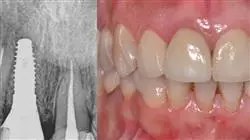

外貌对于人类来说非常重要,口腔的缺陷或问题会直接影响外貌,这个就就更加重要了。因此,近年来种植美学日臻完善,采用了更好的成品假牙和技术,在治疗病症和最终口腔外观方面取得了最佳的效果。

从这个意义上说,患者选择的治疗和制定详尽的种植方案都是关键,最新的诊断和介入技术也非常重要。因此,我们设计了这个 100% 在线大学,为牙科专业人员提供最先进的美学种植知识。